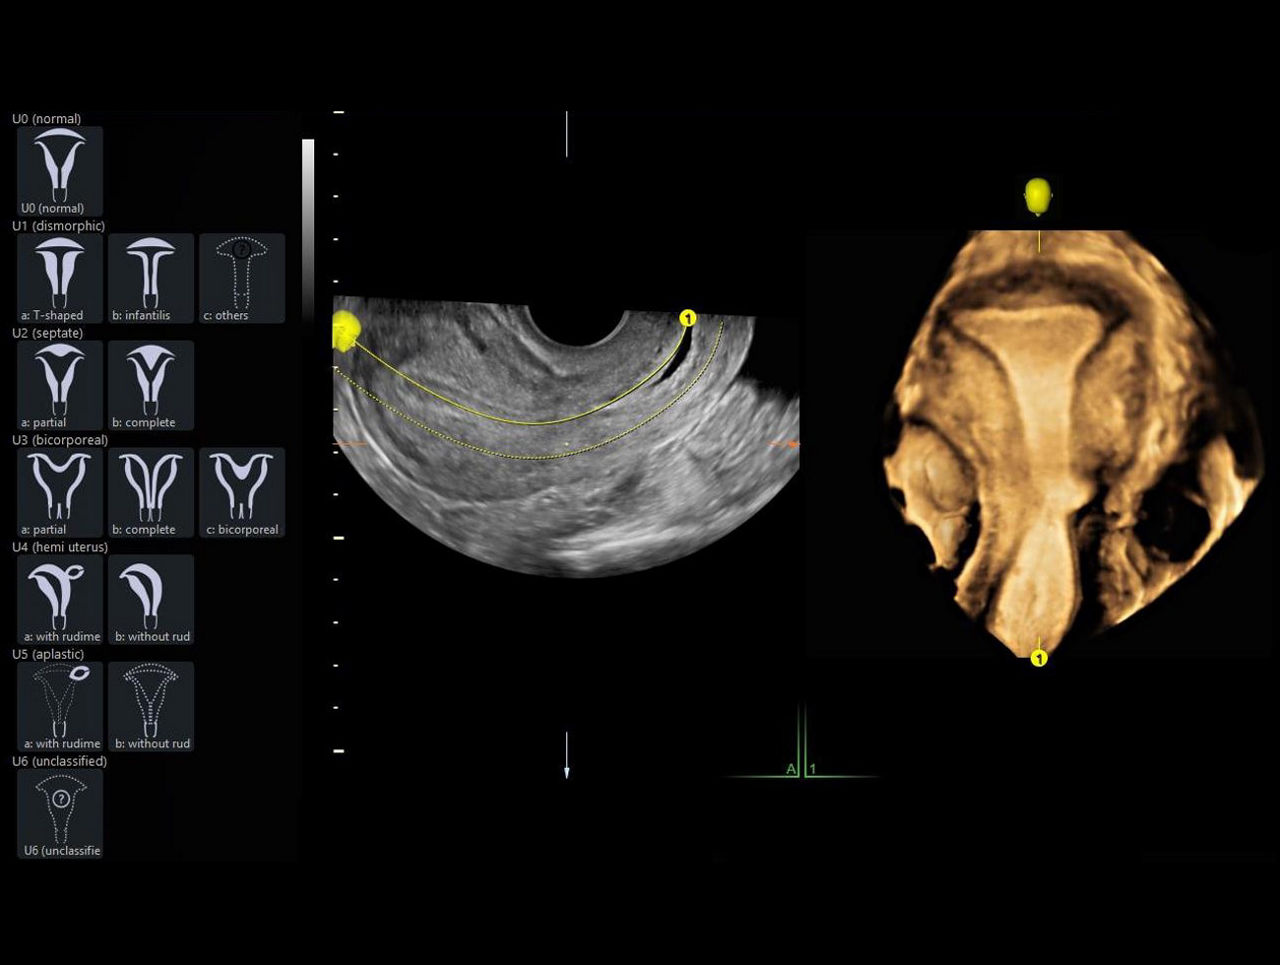

Uterine Classification

Simplify identification and reporting of uterine abnormalities based on ESHRE, ESGE, and ASRM guidelines.